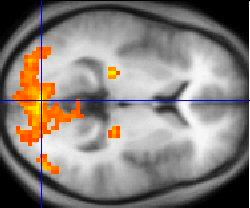

通过fMRI的方式,我们可以很好的判断出大脑此时那些区域是活跃的,但这种活动并不等同于神经活动,但fMRI也有缺陷,即它的成像会损失大量的细节。

如下图,科学家通过fMRI,利用BOLD探索大脑活跃区域。

但从图中可以看出,大脑的细节几乎看不清晰,所以目前常规的方式是使用sMRI对大脑结构进行成像,而fMRI对大脑活跃区域进行成像。